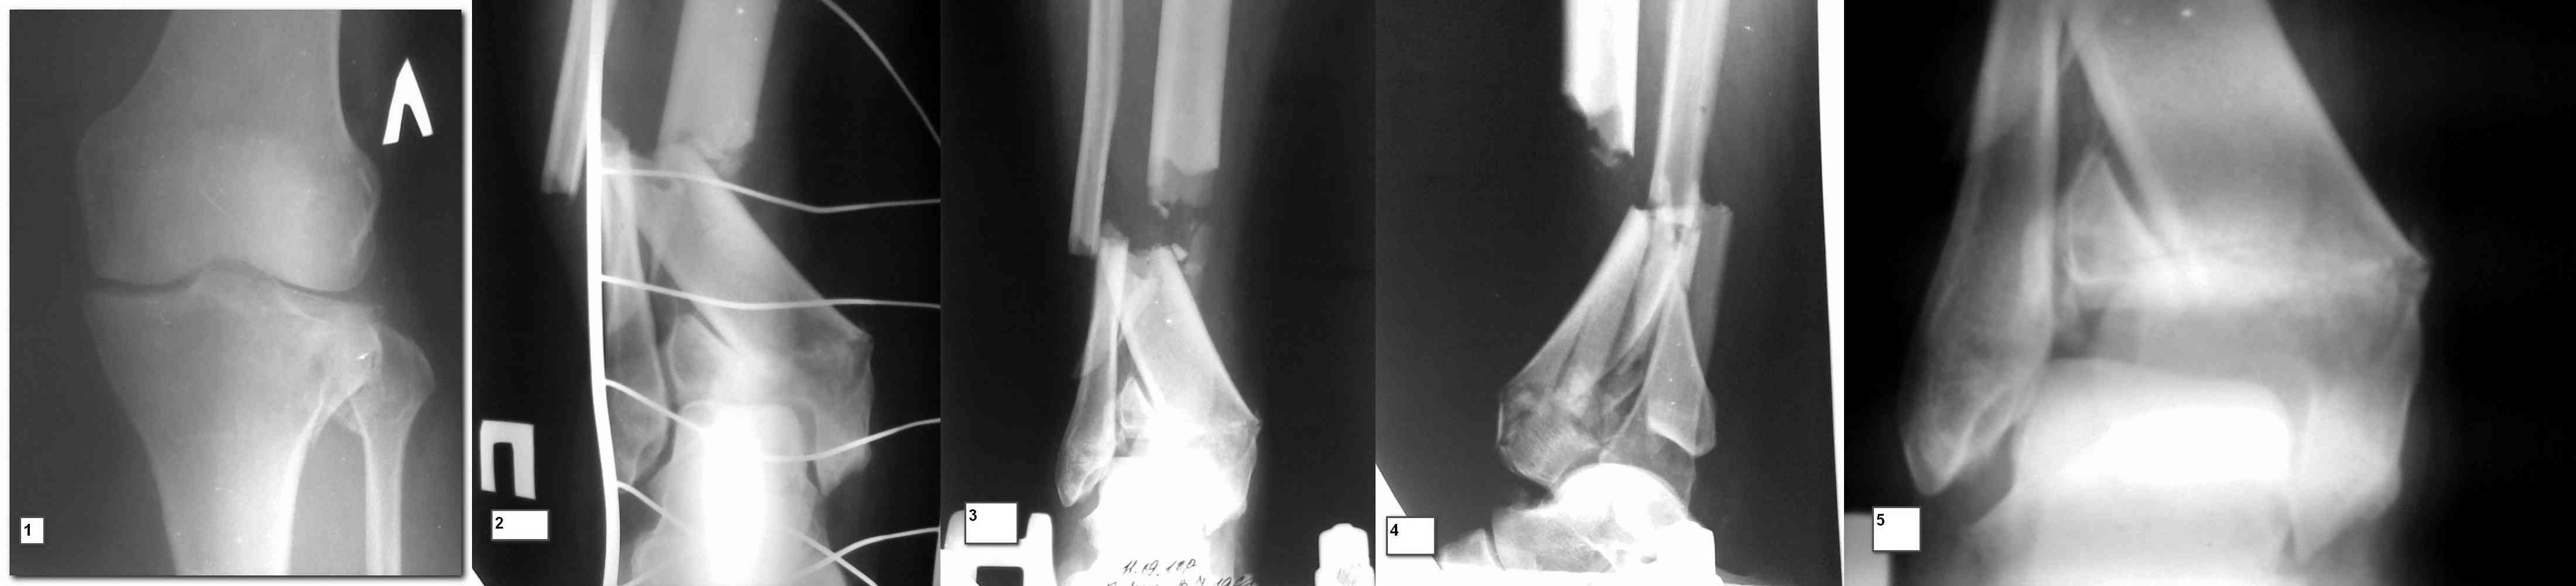

Снимки до и после закрытой репозиции

На представленном после операционном снимке нет репозиции, на что указывает низкое положение тибиального плато и перекрытие кортикальных пластинок в метафизарной части - указано стрелкой. Обычно чрескожную фиксацию я применяю

Пациентки прооперирована, результат чего на снимках. Выполнена открытая репозиция костей правой голени, синтез малоберцевой пластиной, б/берцевой винтами, имеющиеся фиксаторы не подходили, было принято решение репонировать отломки, синтез винтами, гипсовая повязка.

В данный момент локально отёк тыла стопы незначительный, двигательня функция сохранена, ограничена болевым синдромом. Пульсация артерий ослаблена, соответствует левой ноге. Рана - в области границы с пузырём область некроза 2.5*2 см, сухой, не увеличивается, под ним чувствительность сохранена. Чувствительность по всей поверхности кожи в норме, гипоестезия пальцев, при чём варьирует от нормальной, до почти анестезии в течении дня.

Мыщелок левой б/б кости репонирован закрыто, на контрольной рентгенограмме репозиция удовлетворительная, фиксировано спицами. гипсовая повязка.

Репозиция внутрисуставных переломов неудовлетворительная и не адекватна.

Сделайте снимок голеностопа контрлатеральной стороны, перенесите контур сустава на кальку и наложите её на свои послеоперационные Ргграммы - вам станет ясно что нужно сделать и какого стояния отломков достичь. Аналогичный

сценарий и для перелома наружного мыщелка б.б.- передний фрагмент стоит на месте, а задний не репонирован - в таком положении оставлять фрагменты нельзя, суставная поверхность должна быть реконструирована.

При наличии менее агрессивных методов (аппарат) попытка под любым предлогом установить “из того что было в наличии”, и тем более при отсутствии показаний, не считается "благородным делом". Упрямство в лечении внутрисуставных переломов не в интересах больного, и привело к неудовлетворительной фиксации.

В лечении переломов пилона восстановление длины малоберцовой является индикатором и ориентиром для успешного лечения. Первый этап восстановления по длине не удался, малоберцовая остается короткой, и репозиция суставной поверхности осталась неудовлетворительной. Длина передней колонны не восстановлена, а в дистальном фрагменте имеется флексия. Оставлена без внимания потеря кости в метафизе. Шурупы 4.5 мм будут выступать после спадения отека, и возможно будут причиной мягкотканого осложнения в гипсе.